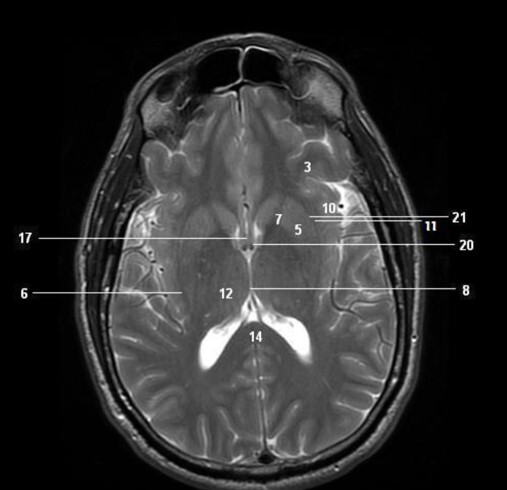

Label 3,5,7,10,11,12,14,20

A

3=Lt frontal lobe

5=Lt Lentiform nucleus

7=Lt internal capsule

10=Insula

11=Lt Claustrum

12=Rt Thalamus

14=Splenium, CC

20=Lt Interventricular foramen